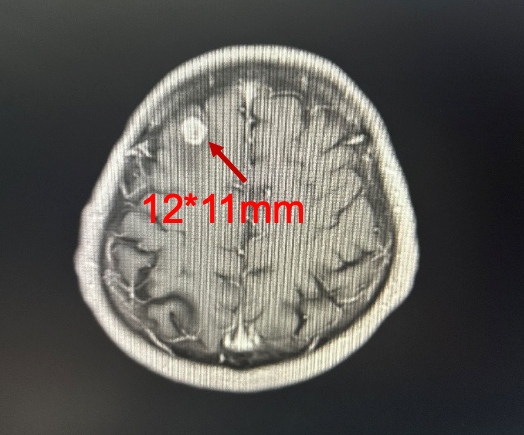

复查胸部CT(2024-10-09)示:与2024-08-08胸部CT检查相比,右肺上叶及右肺门软组织肿物范围较前增大;右肺上叶阻塞性改变较前加重;右肺门及纵隔内部分淋巴结较前增大。

图2 胸部CT(上:2024-08-08,下:2024-10-09)

头颅增强MRI(2024-10-22)示:1.右侧额叶结节,考虑转移瘤伴瘤周水肿;2.双侧额顶叶及侧脑室周围多发异常信号影,考虑脱髓鞘改变。

疗效评估:PD。临床分期:cT2N3M1 Ⅳ期。

PFS2:2个月。